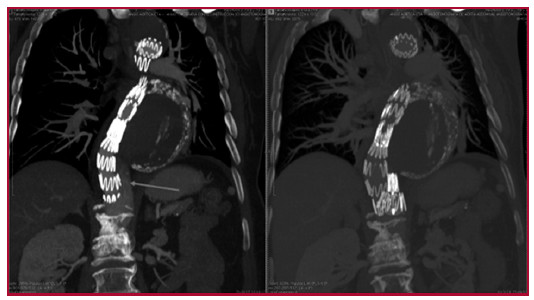

La angiotomografía efectuada al alta no mostró endofuga, con trombosis completa de la falsa luz por encima del dispositivo oclusor (Fig. 2).

Fig. 2. Tomografía preoperatoria (izquierda) y posoperatoria (derecha) con evidencia de flujo en la falsa luz distal (flecha roja), que desaparece luego de colocado el tapón.